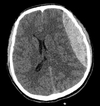

Qual o diagnóstico?

Hemorragia Subaracnóide

sangramento entre a aracnoide e a pia-máter

-Hiperdensidade entre os sulcos, fissuras e cisternas

HSA.